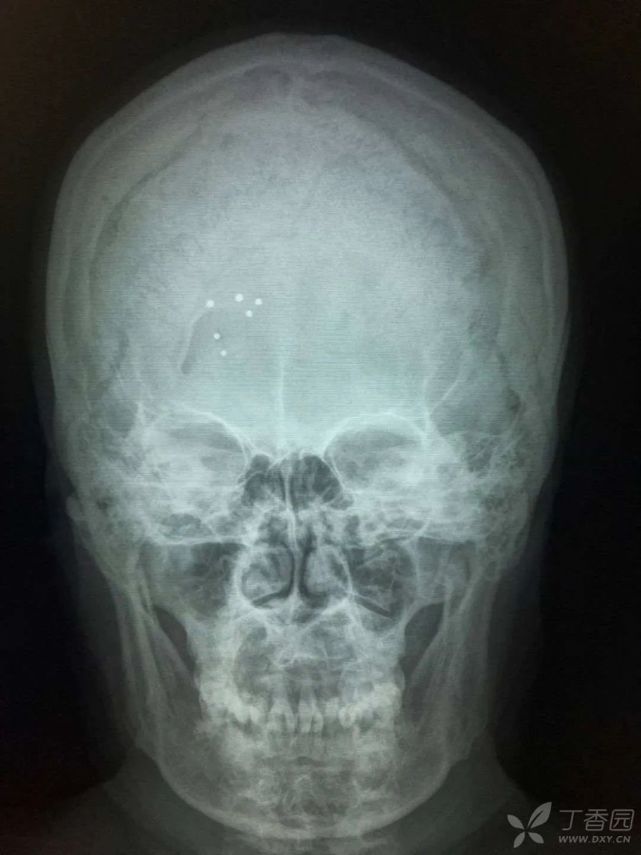

住院期间完善检查结果显示:血常规:WBC 7.4 × 109/L,Hb 62 g/L,PLT 250 × 109/L。尿常规:尿蛋白 3 +,尿隐血 1 +。尿轻链:kap 47.9 mg/L,lam 92.8 mg/L,血轻链:kappa 1.97 g/L,lam 12.2 g/L。生物化学指标:GGT 75 U/L,BUN 18.63 mmol/L,Cr 339 μmol/L。免疫球蛋白:IgA 0.45 g/L,IgM 0.397 g/L。免疫固定电泳:IgG 弱阳性,L 阳性。血清蛋白电泳:Alpha1 5.1%,Alpha2 12.5%,M 蛋白:弱阳性。上腹部彩超:肝光点密集稍粗,胆囊壁毛糙,脾大(21.9 cm × 5.3 cm)。心脏彩超示:左室室壁运动不协调,左室心肌增厚,左房增大,二尖瓣少量返流,主动脉瓣增厚伴少量返流,左室舒张功能减退,微量心包积液,住院期间查头颅正侧位片:额部右侧头皮软组织内多发点状致密影(图 4),颅内未见异常。骨髓细胞学(2015 年 11 月 23 日):增生性贫血、浆细胞比例增高,诊断考虑:浆细胞病待排。2015 年 12 月 22 日再次行骨髓穿刺检查未见明显异常。予输血、促红素等对症治疗后,好转出院。

图片

(图 4 头颅正侧位片)